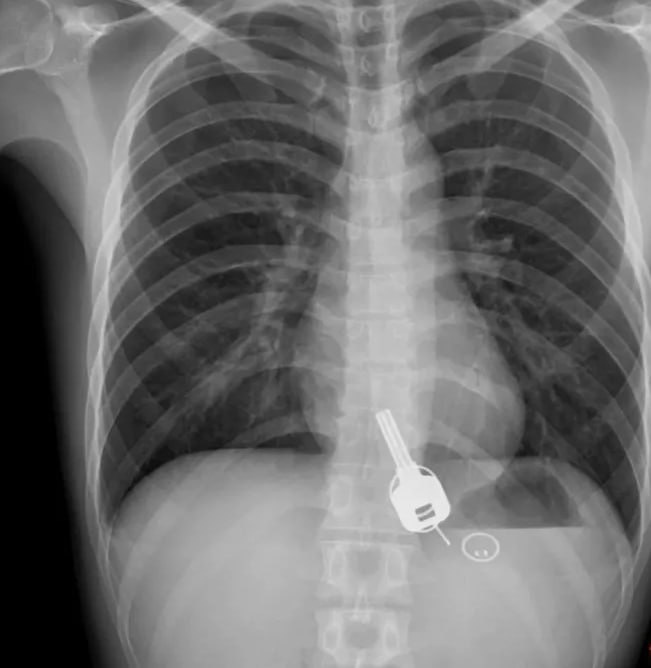

Чтобы папа не уехал на рыбалку, мальчик из Вологодской области проглотил ключ от зажигания мотоцикла. Об этом инциденте сообщили в областном Минздраве. Отец пообещал сыну зоопарк, но собрался на рыбалку. Ребенок решил вопрос кардинально, он проглотил ключ. Врачи детской больницы извлекли инородный предмет. По словам заведующего отделением Игоря Безуглого, такие случаи — частое явление. Ежегодно медики извлекают у детей 40-50 посторонних предметов: от монет до батареек и магнитов, которые особенно опасны. Родители, будьте бдительны! Подписывайтесь 👉 @newsvologda.ru

Чтобы папа не уехал на рыбалку, мальчик из Вологодской области проглотил ключ от зажигания мотоцикла. Об этом инциденте сообщили в областном Минздраве.

Отец пообещал сыну зоопарк, но собрался на рыбалку. Ребенок решил вопрос кардинально, он проглотил ключ. Врачи детской больницы извлекли инородный предмет. По словам заведующего отделением Игоря Безуглого, такие случаи — частое явление. Ежегодно медики извлекают у детей 40-50 посторонних предметов: от монет до батареек и магнитов, которые особенно опасны.